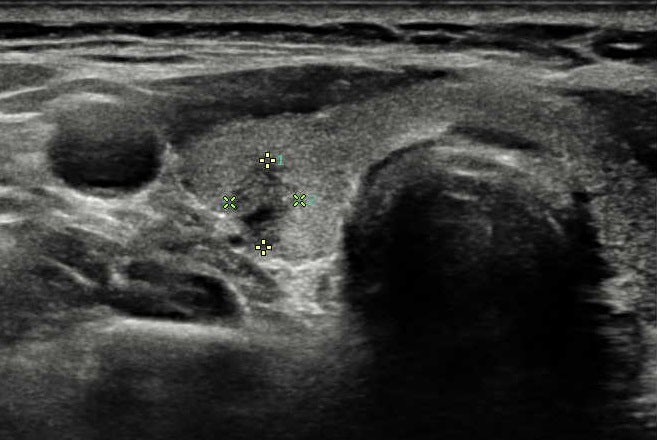

와… 배고픈데… 아무튼 내가 마지막 환자였나봐. 나를 마지막으로 목요일 검사가 모두 끝난 것 같아. 초음파 검사는 항상 긴장되지만 어제도 그랬다. 뭔가 결절이 보이나요?하고 물어보고 싶었지만 의사도 귀찮아 보여 그만 따라붙었다. 뭔가 결절이 보였다면 기계로 사이즈를 체크했을 텐데 딱히 그런 일은 없을 것 같았다. 대화 한마디 없이 초음파 검사는 그렇게 끝났다. 뭐 잘 되니까 말이 없겠지?